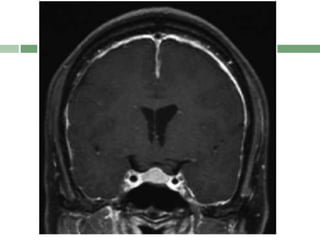

 P- Pituitary enlargement

Acronym : SEEPSfor MRI Features  SEEPS  S- Subdural fluid collections  E- Enhancement of the pachymeninges  E- Engorgement of the venous structures  P- Pituitary enlargement  S- Sagging of the posterior structures